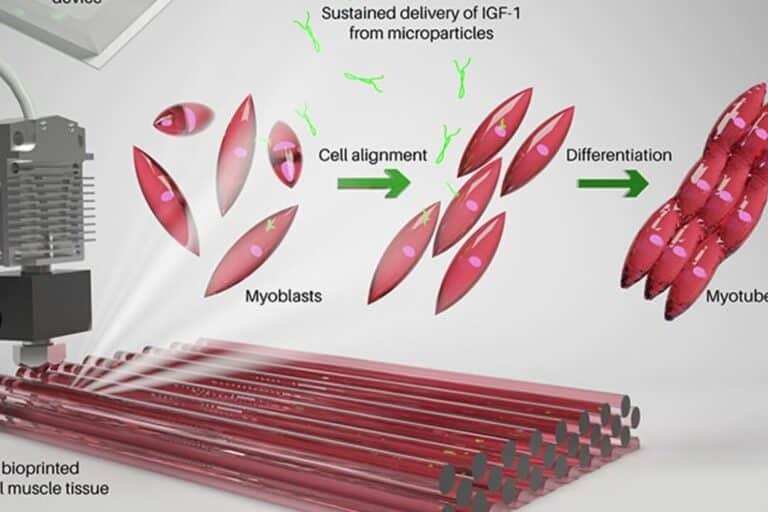

La investigación en ingeniería de tejidos ha alcanzado un hito revolucionario al explorar cómo se crean cuerdas...

La representa un avance revolucionario en la medicina regenerativa. Esta tecnología innovadora utiliza impresoras 3D especializadas para...